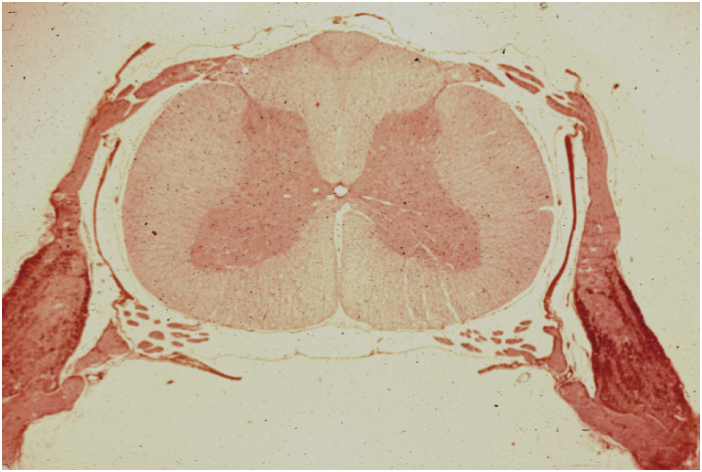

Know your spinal cord – Motor neuron disease

Kultschitzky staining was used here and shows marked symmetrical demyelination (whitening regions) in the anteriolateral roots (especially pyramidal tract) of the spinal cord

It’s day twenty-six already! For those of you who are just finding us, you can find all of the posts in our super cool neuroanatomy category. We’ve already covered a lot of spinal disorders, but one of the larger diseases that we have yet to cover is motor neuron disease. Technically a family of diseases, we will look at the commonalities and causes, so with that introduction, let’s get going.